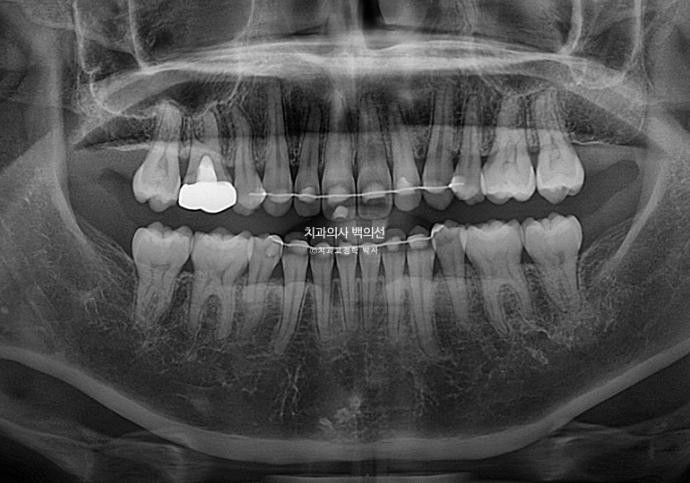

25.04

재교정임에도 치근흡수는 없습니다. 앞니 뿌리를 뼛속으로 넣는 함입이동을 하면 치아 뿌리 짧아지지 않냐고 궁금해하시겠지만 인비절라인은 철사교정처럼 치아에 센힘을 한번에 주지 않아서인지 치근흡수가 잘 일어나지 않습니다.

임상적으로 경험상 느끼는 부분이나 이 부분은 연구가 필요합니다.